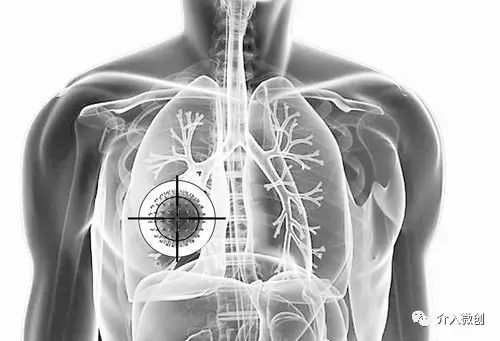

肺转移瘤的介入微创方法主要有:

- 支气管动脉化疗灌注术:有效提高肿瘤局部药物浓度,增强杀灭肿瘤细胞作用。用药量少,全身不良反应小;

- 支气管动脉化疗栓塞术:可精确栓塞肿瘤供血动脉,促进肿瘤坏死;

- 经皮肺穿微波/射频消融术:微创、快速消减瘤体负荷;

- 放射性粒子植入术:植入放射性粒子,可持续、近距离照射肿瘤,对周围正常组织损伤小。